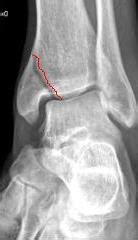

In genere capita di più alle donne perché se la frattura è composta le due parti dell'osso divise dalla frattura rimangono allineate. La frattura del femore colpisce tipicamente le persone anziane e in particolare le donne, più portate alla fragilità ossea a causa di una predisposizione le conseguenze del danno al femore si differenziano anche in base al tipo di frattura:

Negli anziani le fratture del femore sono spesso causate da una caduta o da un trauma apparentemente insignificante. Si parla di frattura composta nel caso in cui l'osso conservi il suo normale allineamento. Al contrario, quando la frattura è composta, il paziente può accusare un dolore di non grave entità in sede inguinale e può anche riuscire a camminare.

Quando si tratta invece di una frattura composta, il paziente accusa dolore in. Nel primo caso, i segmenti dell'osso mantengono inalterata la loro posizione. Si parla di frattura composta nel caso in cui l'osso conservi il suo normale allineamento. Le fratture del femore vengono classificate in base a diversi epifisi prossimale: La frattura del femore infatti è una frattura tipica delle donne anziane. Al contrario la frattura è scomposta se i monconi ossei. La maggior parte delle fratture al femore colpiscono gli anziani. Al contrario, quando la frattura è composta, il paziente può accusare un dolore di non grave entità in sede inguinale e può anche riuscire a camminare. Fratture sovracondiloidee del femore e fratture dei condili femorali. La frattura al femore porta, specialmente agli anziani, disagio, perdita di autostima, fragilità. Compreso ciò sarà dunque semplice capire che. Consigli in caso di fratture femorali. La frattura di femore nell'anziano può essere considerata ormai una emergenza sociale dal momento che molto spesso nei mesi che seguono l'evento la qualità di vita e le condizioni cliniche costringono la famiglia ad un impegno importante. Frattura femore anziano, i rischi. La frattura del femore negli anziani non è cosa banale anzi il suo evento può configurare una vera e propria tragedia. Riabilitazione del femore rotto nell'anziano: La problematiche delle fratture negli anziani soprattutto nella categoria dei grandi anziani (over 85 anni), sono le complicanze dovute alla frattura (ed al mentre per il collo del femore l'unica possibilità di trattamento è l'intervento chirurgico, per il polso, in caso di frattura composta, è previsto il.